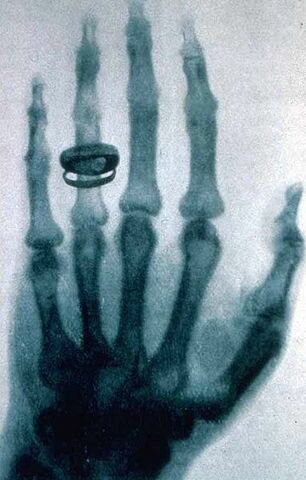

• RAIG X

RAIG X

Roentgen va ser el investigador i dexcobridor dels raigs X. Els raigs X son radiacions electromacnetiques invisibles que travessen capes. El 22 de desembre Roetngen va fer la primera radiografia del mon a la seva dona, on apareix la fotografia amb el anell posat